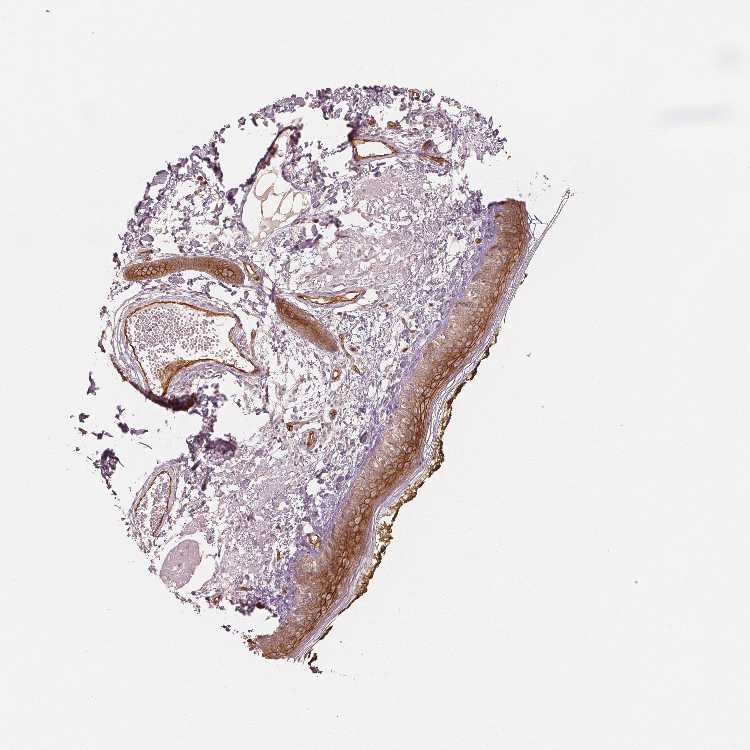

SKIN 1 - Antibody stainingi

Antibody staining in the annotated cell types in the current human tissue is reported as not detected, low, medium, or high, based on conventional immunohistochemistry profiling in selected tissues. This score is based on the combination of the staining intensity and fraction of stained cells.

Each image is clickable and will lead to virtual microscopy that enables deeper exploration of all samples and also displays staining intensity scores, fraction scores and subcellular localization as well as patient and tissue information for each sample.

Antibody HPA042413Antibody HPA074310Antibody CAB012991

Langerhans Not detectedMediumLow

Fibroblasts Not detectedMediumLow

Keratinocytes Not detectedLowMedium

Melanocytes Not detectedMediumLow

SKIN 2 - Antibody stainingi

Epidermal cells Not detectedMediumMedium